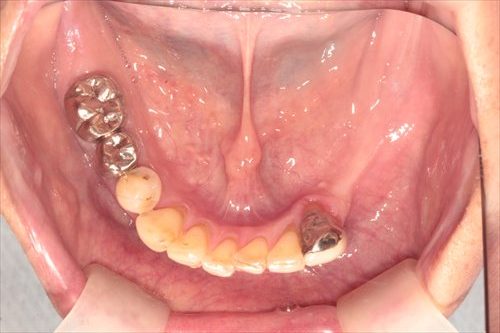

レントゲンを診て悩みました。左右的すれ違い咬合だったからです。

この方の場合で言うと、左(写真向かって右)では上の歯だけ、右(写真向かって左)では下の歯だけが残っているような状態です。

術前です。